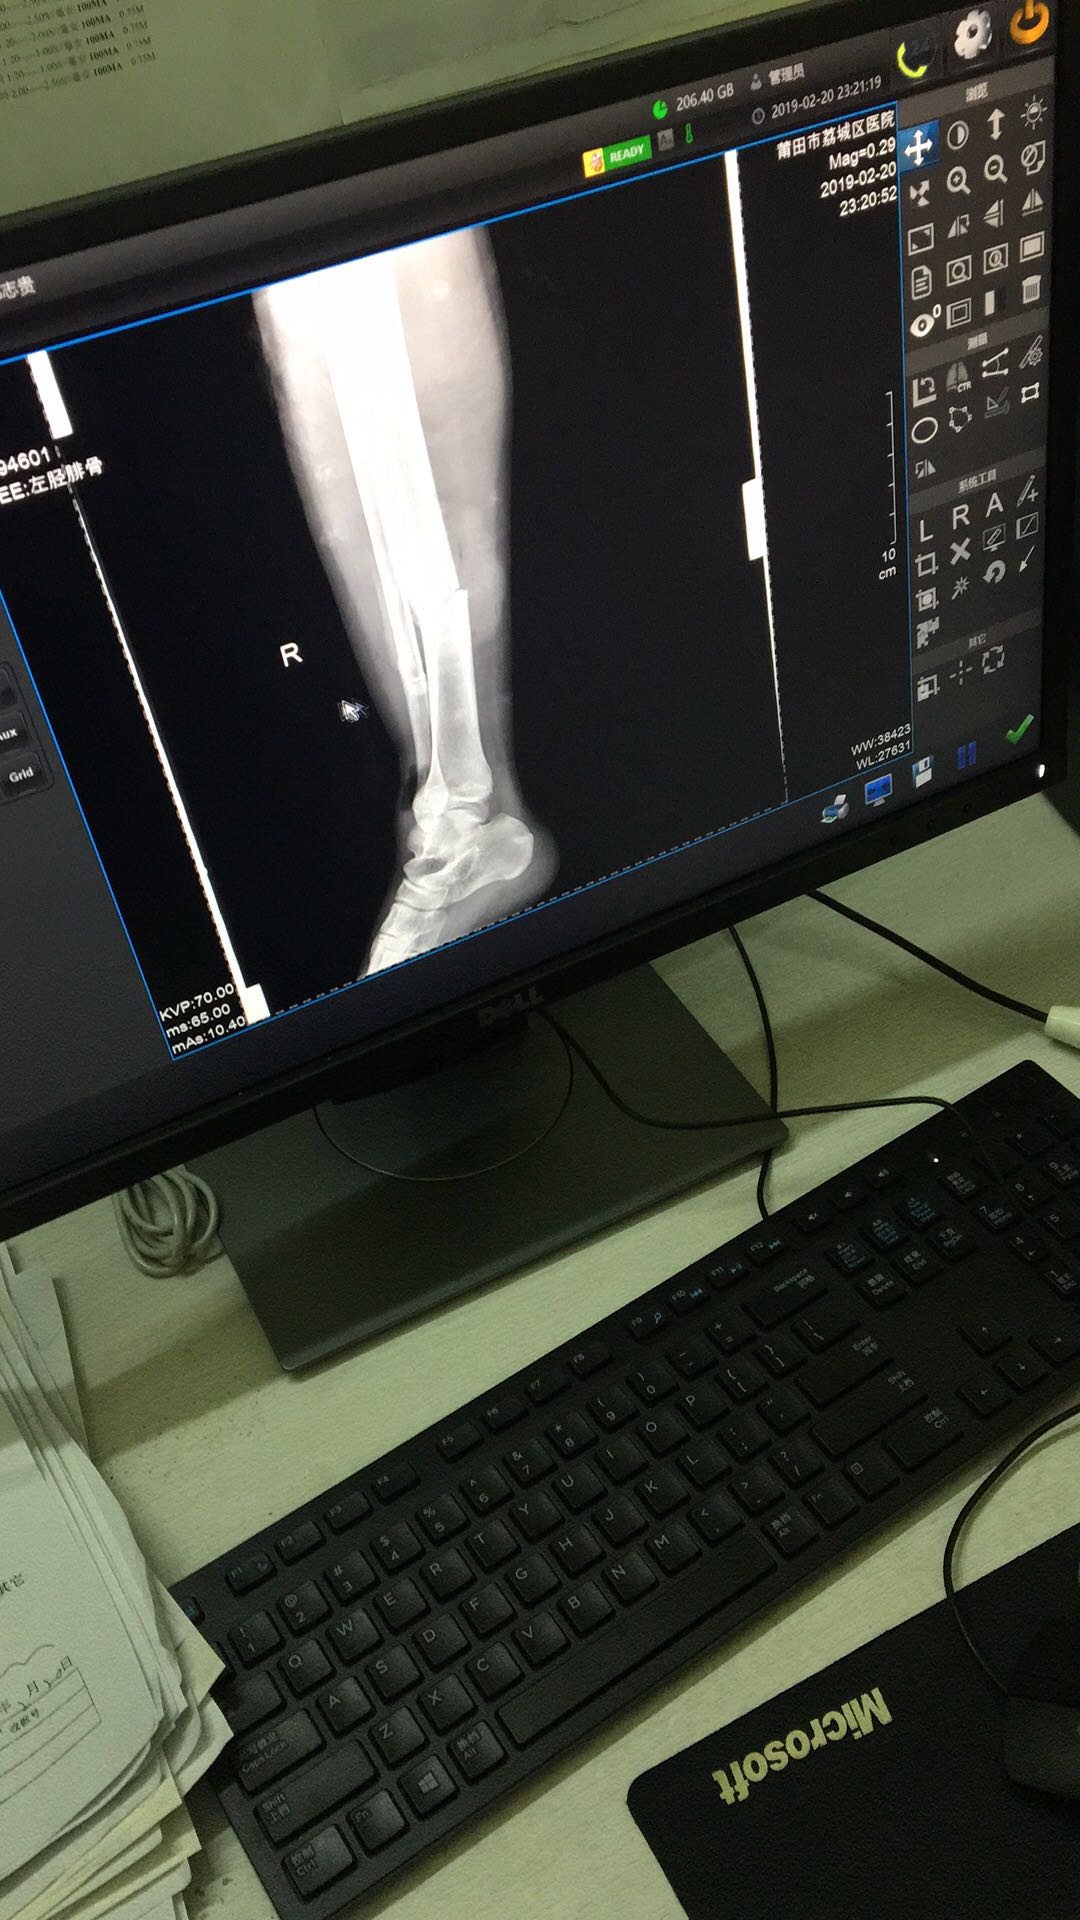

20号晚上出车祸,骨折了,然后脚肿胀不能做手术,今天拆开纱布

20号晚上出车祸,骨折了,然后脚肿胀不能做手术,今天拆开纱布发现骨折周围地方起一大片水泡